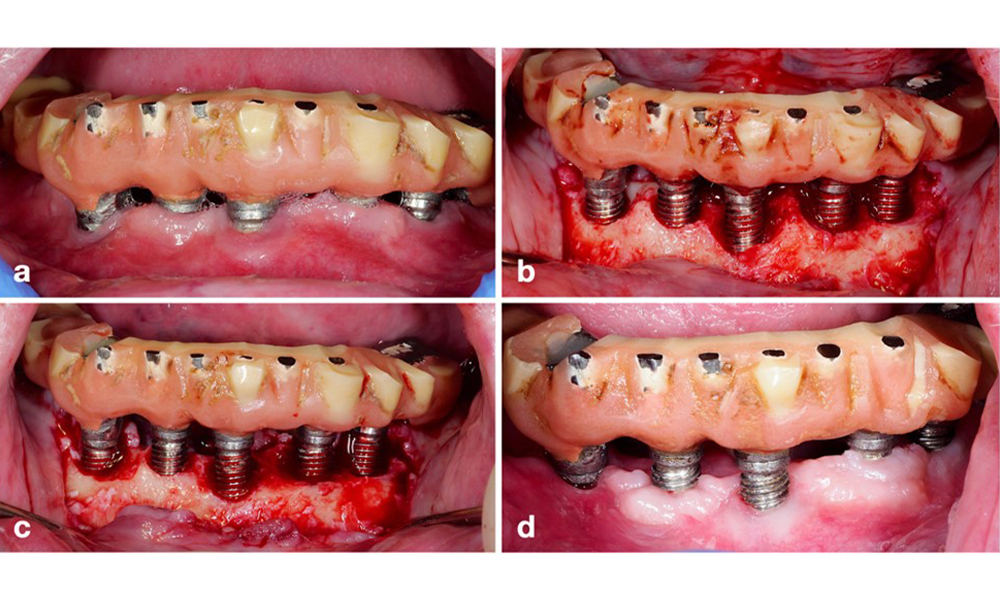

Restauration de l'arcade complète avec péri-implantite à des degrés divers sur certains implants. L'implant en position 21 est sévèrement atteint avec des profondeurs de sondage allant jusqu'à 9 mm (a), un saignement au sondage, une suppuration du sillon péri-implantaire et une fistule vestibulaire (b-c) ; la radiographie montre une perte osseuse d'environ 50 % pour l'implant atteint de péri-implantite en position 21, tandis que l'implant en position 23 présente une perte osseuse limitée, correspondant approximativement à ce que l'on peut attendre après la cicatrisation initiale pour ce type d'implants (d).

Figure 2. Restauration de l'arcade complète avec péri-implantite à des degrés divers sur certains implants. L'implant en position 21 est sévèrement atteint avec des profondeurs de sondage allant jusqu'à 9 mm (a), un saignement au sondage, une suppuration du sillon péri-implantaire et une fistule vestibulaire (b-c) ; la radiographie montre une perte osseuse d'environ 50 % pour l'implant atteint de péri-implantite en position 21, tandis que l'implant en position 23 présente une perte osseuse limitée, correspondant approximativement à ce que l'on peut attendre après la cicatrisation initiale pour ce type d'implants (d).